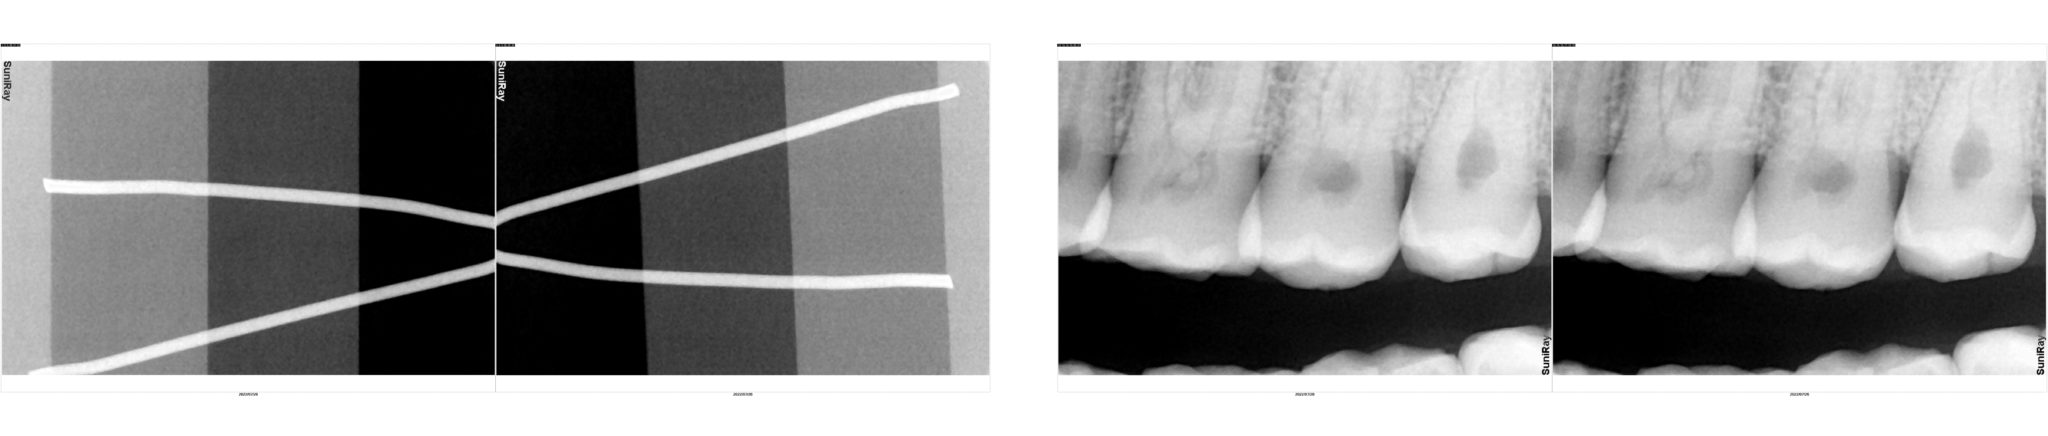

Please view the x-rays attached to this sensor before purchasing. Pre-Owned sensors may have imperfections in the image e.g. line, ghost image, dead pixels, or noise. Please ensure the image quality meets your standards.

-Sensor is tested by taking 36 X-rays on a Phantom to ensure sensor functionality

Pre-Owned sensors may have artifacts in the image, please review the example images provided that were taken from the sensor prior to its sale. Tube heads or choice of exposure will affect the contrast, brightness and clarity of the image. Sodium Dental is not responsible for this. Any return of product will be subject to a 15% restocking fee and no refund of shipping.